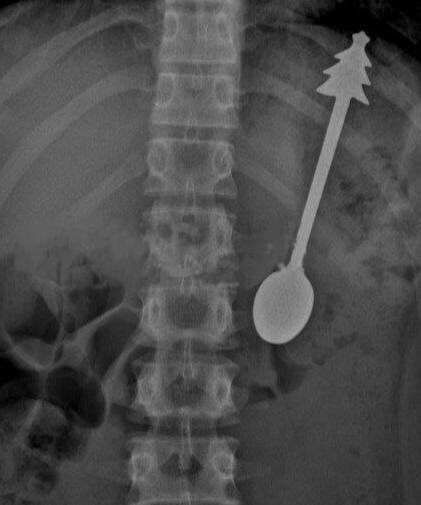

Ребенок случайно проглотил 14-сантиметровую ложку в Оренбурге

Его срочно доставили в больницу, где провели операцию по удалению столового прибора с елочкой на ручке. Все прошло успешно, и уже на следующий день ребенка отпустили домой. Сальное Дифлопэ

Его срочно доставили в больницу, где провели операцию по удалению столового прибора с елочкой на ручке. Все прошло успешно, и уже на следующий день ребенка отпустили домой.